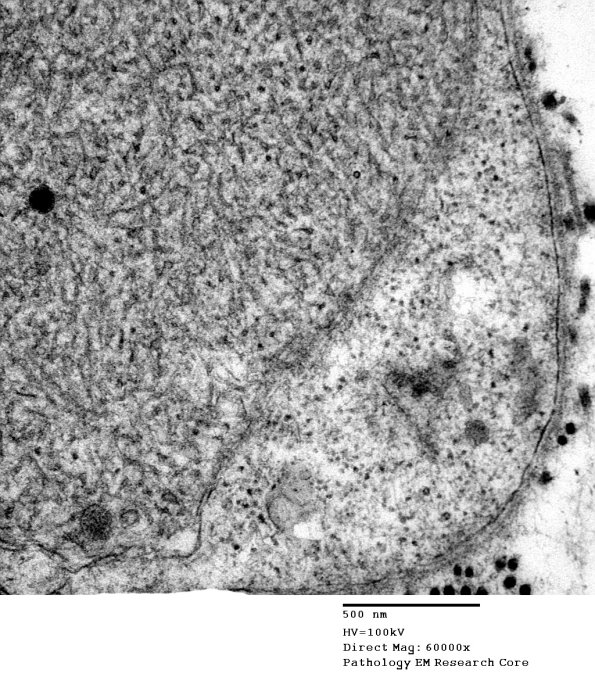

3B6C Axonal regeneration, SLE NP Vasculitis (Case 1)_061 - Copy

Higher magnification of image #3B6B. (electron micrograph)